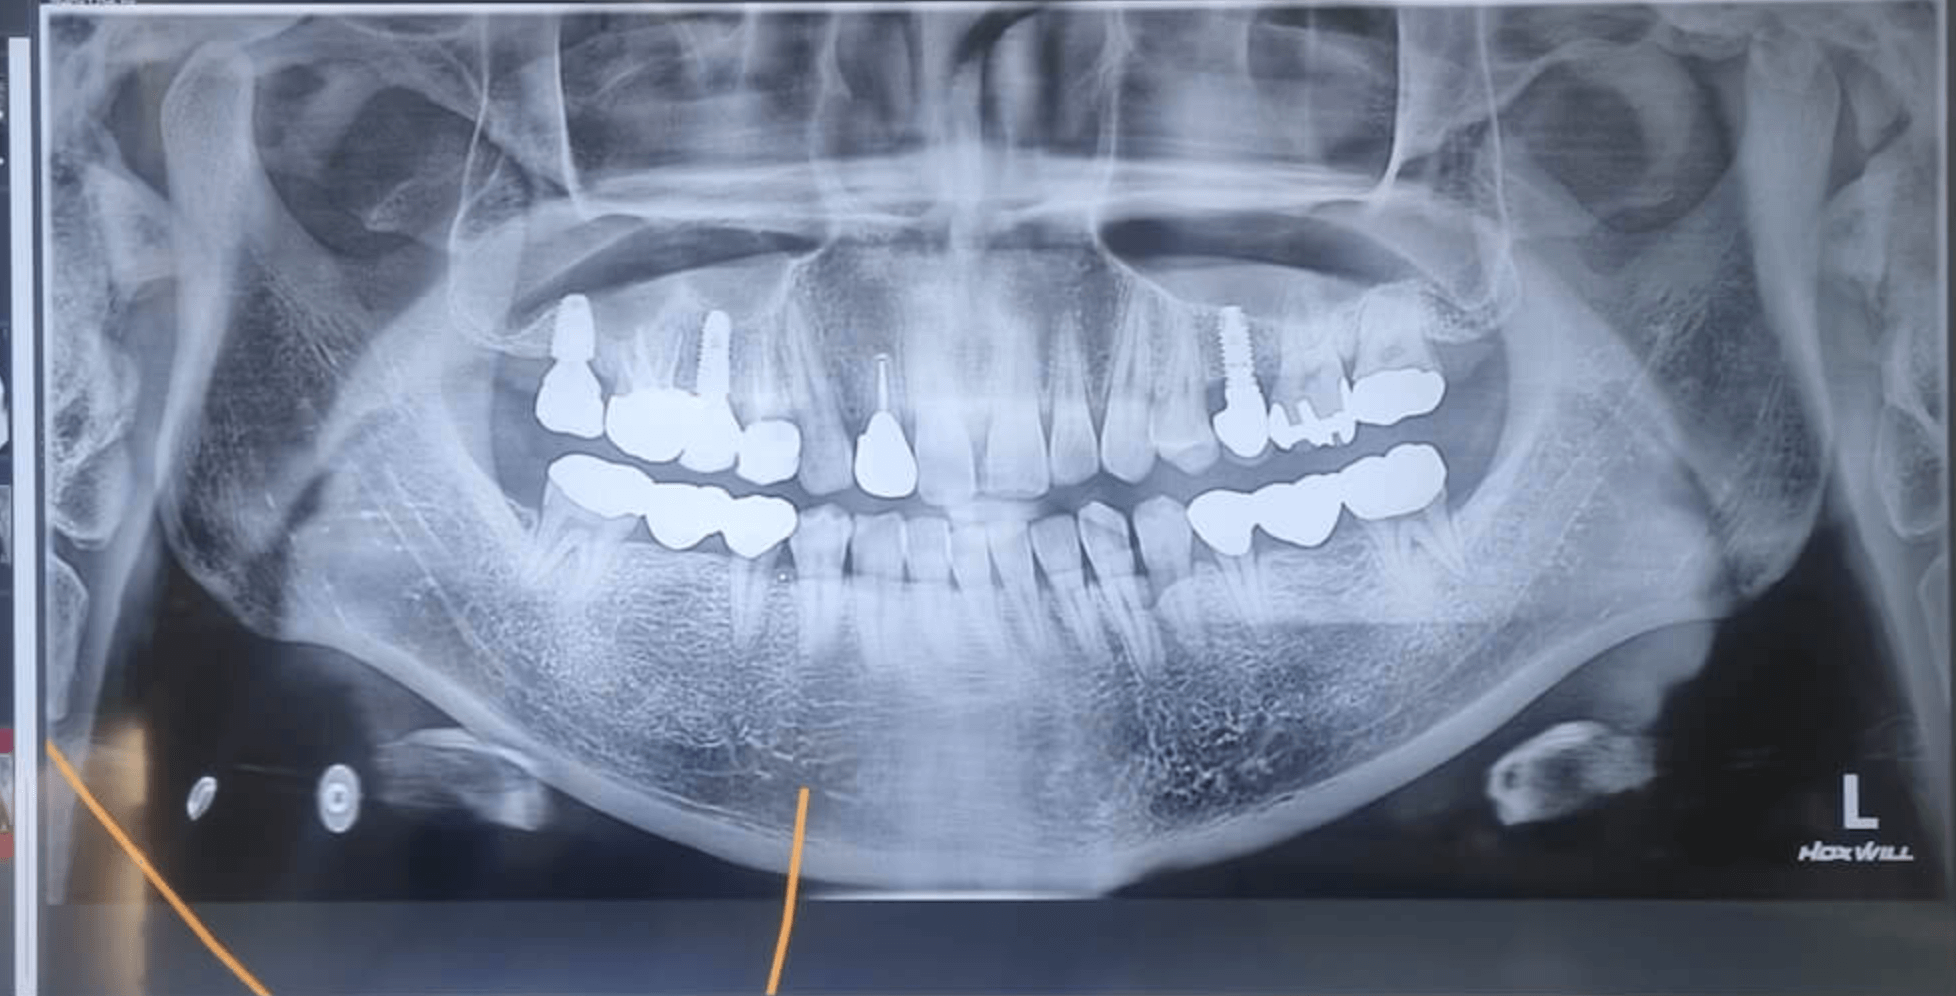

글쓴이는 어릴때부터 치아가 별로 좋지 않아서, 최근 20-30년 지나다 보니 새롭게 해 넣어야 되는 치아들이 많았고, 염증으로 인해 임플란트를 해야 하는 경우가 자꾸 발생했습니다.

치과에서 보면 VIP 고객이라고 생각하면 될만큼 자주 치과를 방문했고, 지금도 이전에 치료했던 치아가 수명을 다해가는 게 많아서 쭈욱 치과 치료를 해야 합니다. 앞니 지르코니아 크라운 같은 경우는 크게 씹을 일이 없어서 깨짐이나 이런 것은 발생하지 않았습니다.

금니를 이야기 할려고 하니깐, 방긋 웃음이 나옵니다. 어릴적 26년 전 해 넣은 어금니 브릿지중 한개가 구멍이 나서 교체를 한 것이 지르코니아 브릿지 인데 1년만에 고생만 했고, 아직 26년이 지난 금니 브릿지 하나는 그대로 잘 사용하고 있습니다.